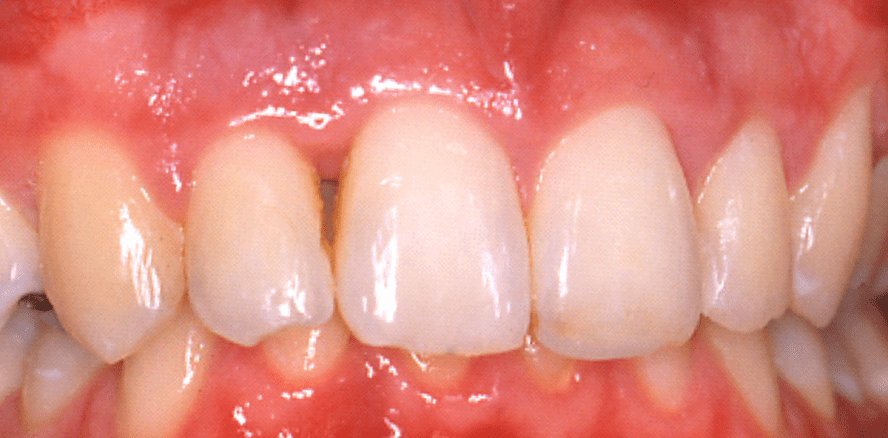

Der 21-jährige Patient befindet sich seit 1999 bis heute aufgrund einer generalisierten aggressiven Parodontitis in der Erhaltungstherapie im Zentrum für Zahn-, Mund- und Kieferheilkunde der Universitätsmedizin Greifswald (Abb. 1 bis 4). Erstmalig stellte sich der Patient im Schmerzdienst mit einer Überweisung des Hauszahnarztes nach einer abgeschlossenen kieferorthopädischen Behandlung im Januar 1999 vor. Zu diesem Zeitpunkt litt der Patient an akuten Beschwerden im Bereich aller Parodontien des Ober- und Unterkie­-fers mit spontanem putriden Exsudat an 16, 26 und 46 (Abb. 4). Die Gingiva war an allen Zähnen geschwollen, entzündet und blutete auf Sondierung. Die Nahrungsaufnahme war durch Schmerzen und Zahnlockerung der Zähne 11 und 12 stark eingeschränkt (Abb. 2, 4).